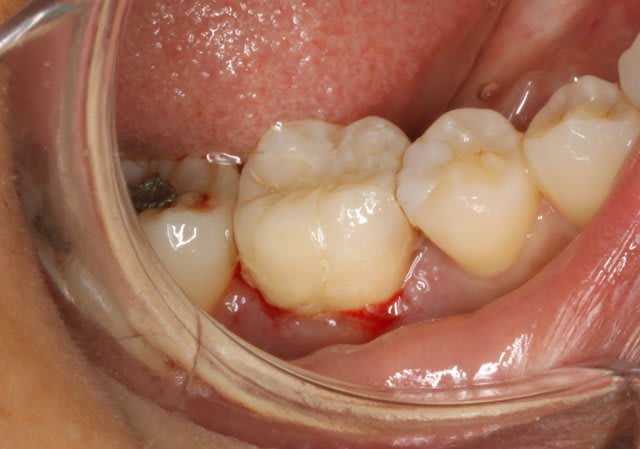

Un petit onlay du dimanche dernier qui m'a fait plaisir. A souligner le travail du prothésiste, content de son boulot après avoir vu les photos.

Pour Sethef: la digue (medium) ne m'a pas gêné, mais le premier clamp que j'ai voulu mettre remontait partiellement sur la limite.

La cavité d'accès pour une dévit est insuffisante , la dent est vivante . La limite de la cavité est sus gingivale .

Dent vitale. Il y avait un compo OD et le pan V a lâcher. Limite supra-gingivale.

Ci joint une autre vue.